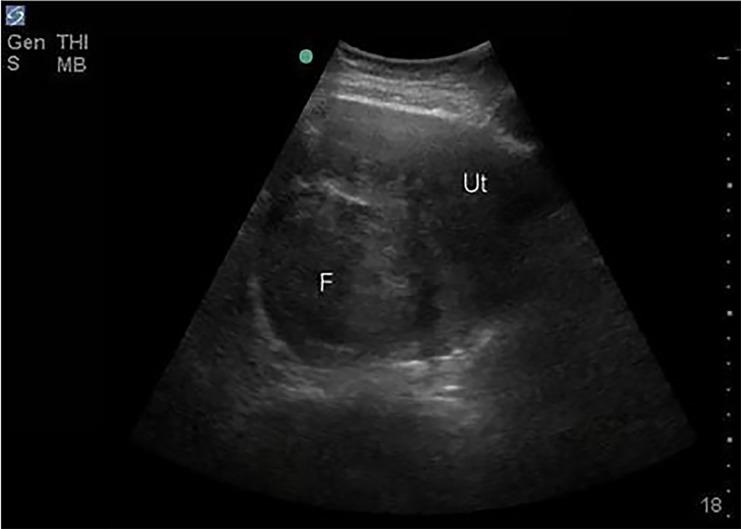

A young woman presented to the emergency department with lethargy, hemodynamic instability, and diffuse abdominal tenderness. On point-of-care ultrasound (PoCUS), she was found to have intraperitoneal free fluid and a large pelvic mass, which were discovered intraoperatively to be hemoperitoneum due to ruptured vessels of a uterine leiomyoma. Although rare, a life-threatening, ruptured leiomyoma may be treated surgically if recognized in an expedient fashion. A PoCUS can aid the emergency clinician in prompt diagnosis.

一名年轻女性因嗜睡、血流动力学不稳定和全腹压痛就诊于急诊科。床旁超声(PoCUS)检查发现她有腹腔内游离液体和一个巨大盆腔肿块,术中发现是子宫平滑肌瘤血管破裂导致的腹腔积血。虽然罕见,但如果能及时识别,危及生命的破裂平滑肌瘤可通过手术治疗。床旁超声可帮助急诊医生进行快速诊断。